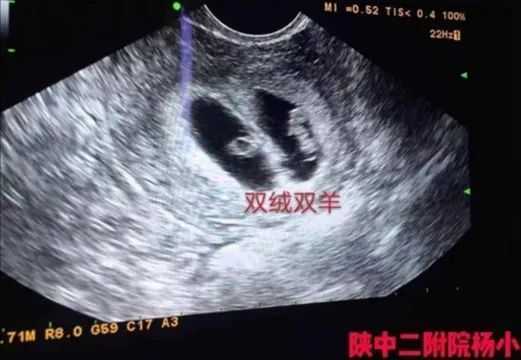

术前超声

看着患者恳求的目光,杨小颀一边鼓励安慰,一边邀请到超声科主任杨兵社进行会诊,确定患者分裂的胚胎为双绒双羊。双绒双羊就是双绒毛膜双羊膜囊,不是两个宝宝共用一个胎盘,就是双卵双胎,两个宝宝分别在自己的羊膜腔内。这种情况,一般多数是两个卵,两个胚胎,也有一个卵两个胚胎的情况,但是是少数。